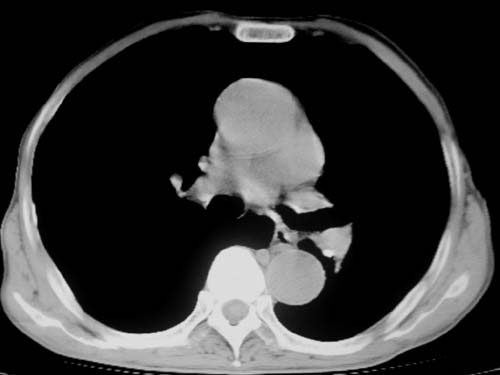

标题: CT19736:男,76岁,咳嗽,胸痛 [打印本页]

标题: CT19736:男,76岁,咳嗽,胸痛

支持左上肺周围型肺癌性并空洞形成伴胸椎转移。

左上沟癌空洞形成并胸椎转移。

考虑癌性空洞并胸椎转移。

空洞内壁有多发结节,支持癌性空洞。